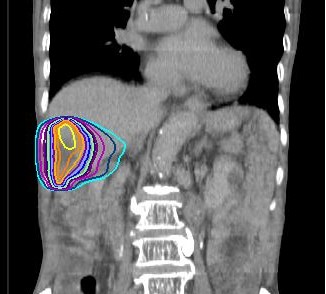

当科では治療用のCT(富士フィルム SCENARIA64列)、3次元治療計画装置(Ray Search社 Ray Plan)、ライナック(ELEKTA社 Precise Treatment System)が設置されています。CTシミュレーターを用いた3次元治療計画を行い、多方向から病巣へ線量を集中させて最大限の効果をねらうと同時に、周囲臓器への被曝を減らして副作用を最小限に止めるよう努めています。

肝臓がんに対する治療計画の線量分布図